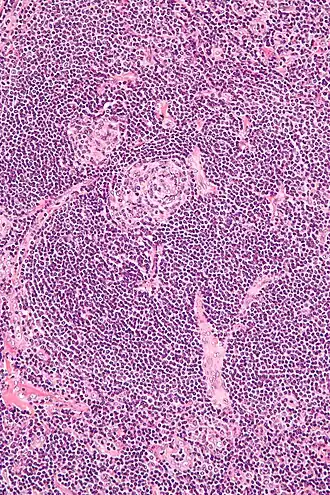

![]() Micrografía de la variante vascular hialina. | ||